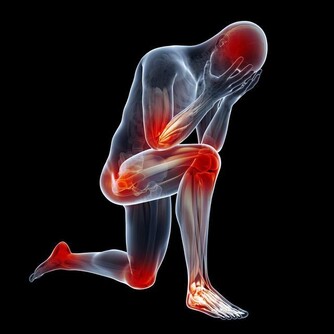

鼻子是我們夜間呼吸的主要通道,一旦鼻腔因為鼻炎發作,出現腺樣體肥大,

導致進入鼻腔的氣流受限,病人氣道通氣量減少,出現機體的慢性缺氧。

寶寶為啥會有黑眼圈? 家長要引起注意了!

這個時候,很多患者就會使用嘴部張口呼吸,出現睡覺打呼嚕的症狀。而長期張口呼吸會使上下頜咬合關係發生變化,導致兒童上下頜發育不良,可能出現面部拉長、嘴唇增厚症狀,直接影響面容。